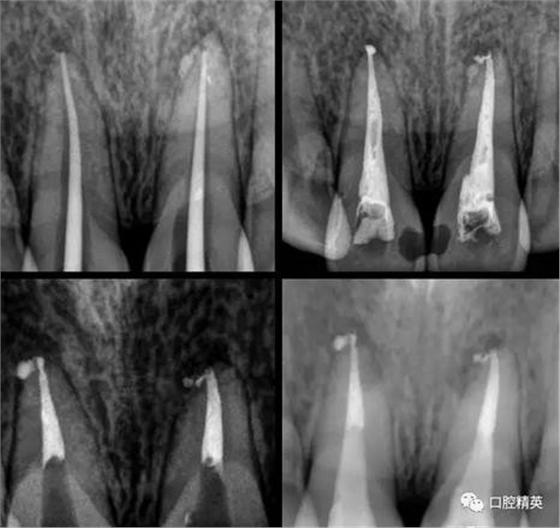

處理:(初診)取原始模型,11,21開(kāi)髓,拔髓,擴(kuò)根,沖洗,CP碘仿棉捻開(kāi)放。

(二診)取出開(kāi)放物,雙氧水沖洗,氫氧化鈣糊劑加碘仿暫封2周。

(三診) 去除暫封物及糊劑,鹽水沖洗,隔濕,干燥,大錐度牙膠尖配合樹(shù)脂根充糊劑行根管充填,一周后復(fù)診。

(四診)11,21唇側(cè)膿腫基本消除,叩(-),預(yù)備樁道,置入纖維樁,備牙,取模,翻制臨時(shí)冠。

術(shù)中根管治療,置人纖維樁,牙體預(yù)備,臨時(shí)冠修復(fù)